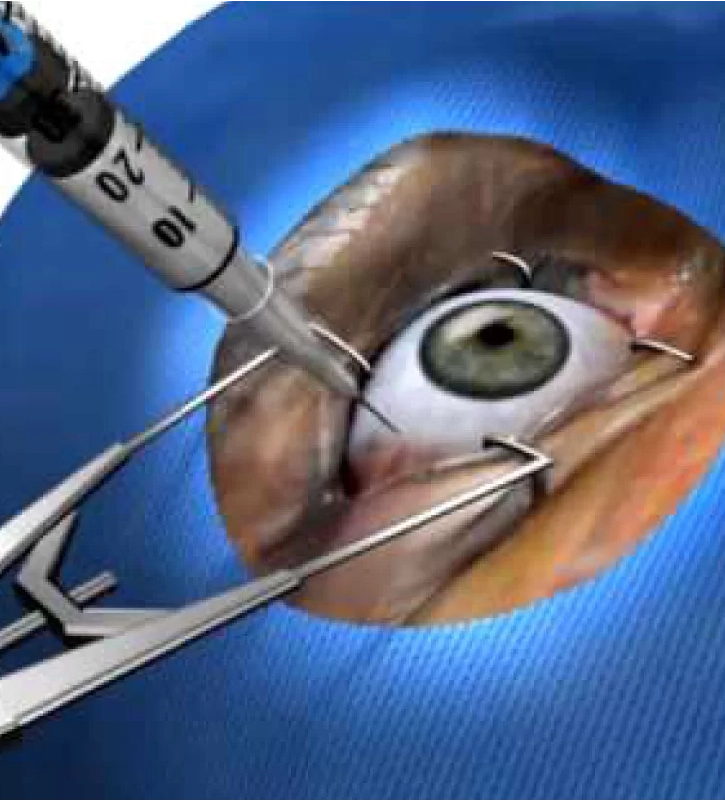

CIRUGÍA DE CATARATA

CIRUGÍA DE CATARATA

Usamos la última tecnología para eliminar las Cataratas de forma segura. Sin estadía.